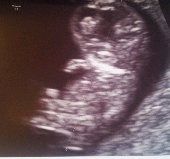

Foto's van mini, hier 9 weken en 4 dagen...